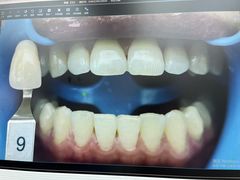

• -牙博士口腔品牌连锁(杨浦店)

CoeY.Sept.4 | 24-06-29

报错